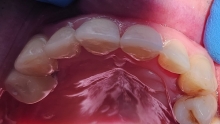

Semnele aparitiei paradontozei:

– gingiile sangereaza la periaj;

– gingii rosii si inflamate;

– mobilitatea sau deplasarea dintilor;

– retractii gingivale cu expunerea radacinilor dentare;

– halena.